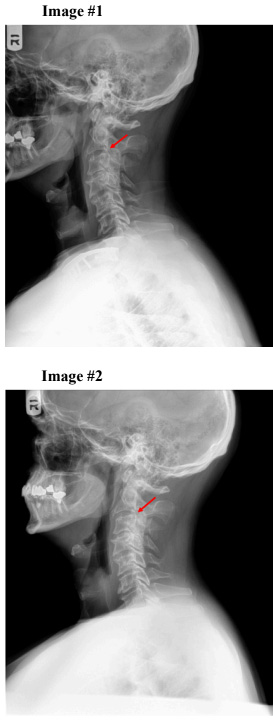

X-ray Findings (Taken on 9/19/2024):

- Grade 2 anterolisthesis of C2 on C3 was noted disturbing George’s line.(see images #1)

- Other findings not noted in this study